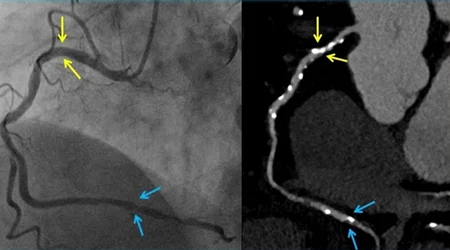

آنژیوگرافی یک تست تشخیصی است که برای تشخیص بیماری های قلبی انجام می شود. هدف اصلی از آنژیوگرافی عروق کرونر ، تشخیص تنگی و انسداد عروق کرونر قلب است ، ولی موارد دیگری هم وجود دارند که برای تشخیص آنها احتیاج به انجام آنژیوگرافی قلب است. بیماری هایی مانند تنگی و نارسایی دریچه های قلبی ، اندازه گیری مستقیم فشار داخل حفرات قلب و شریان ریوی ، تشخیص و ارزیابی شدت بیماری های مادرزادی قلب و برخی بیماری های دیگر قلبی و عروقی.